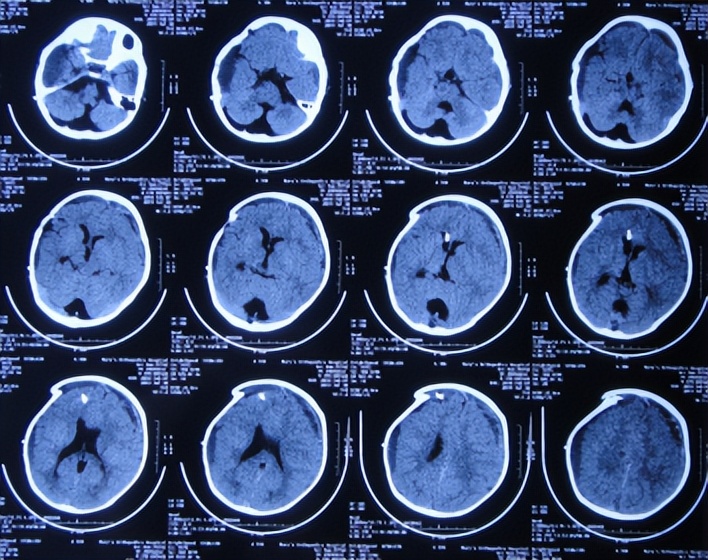

2018年9月27日(蛛网膜囊肿脑池沟通术后9天),查头颅CT示硬膜下积液反增多( 图-4 )。

图-4: 2018年9月27日头颅CT